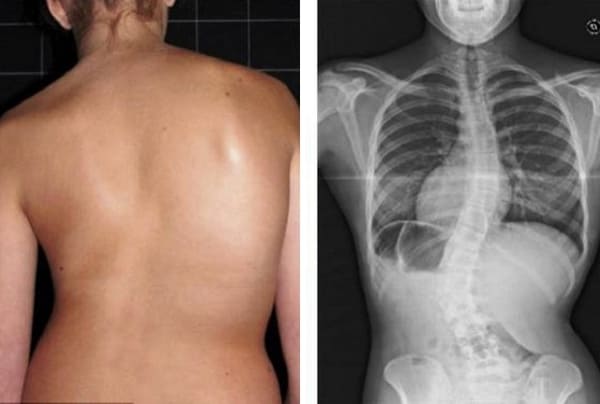

Quyidagi suratlarga qarang. Belgilarga e’tibor bermaganlarning boshiga nimalar tushganini ko‘ring. Bugun bu odamlar umidsiz holatda, ularning ko‘pchiligida yordam so‘rashga ham odam qolmagan. Siz ham o‘zingizga bunday taqdirni ravo ko‘rasizmi?

52 yoshli ayol. Orqa umurtqa diskining siljishi va og‘ir deformatsiyasi, asablar siqilishi va orqa miyaga shikast yetgan.

“Beva qiyshig‘i” — umurtqalarning deformatsiyasi va har kuni kuchayib borayotgan surunkali, chidab bo‘lmas og‘riq.

Erkak, 37 yosh. “Joint Solve” preparati yordamida faqat bitta kursda to‘liq qomat tuzatildi.